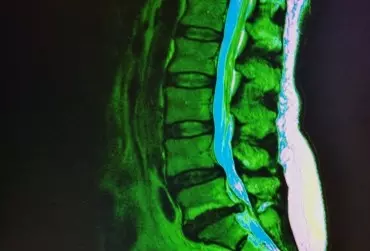

Diagnostyka różnicowa odcinka lędźwiowego kręgosłupa i stawu krzyżowo-biodrowego - Część 1

Dolegliwości bólowe w obrębie odcinka lędźwiowego kręgosłupa dotykają dużej części populacji. Przyczyną bólu mogą być zarówno zmiany zwyrodnieniowe, urazowe, jak i inne schorzenia. W artykule szczegółowo przedstawiono krok po kroku diagnostykę odcinka lędźwiowego kręgosłupa i stawu krzyżowo-biodrowego. Prawidłowe rozpoznanie przyczyny bólu i wdrożenie odpowiedniej terapii zapobiega coraz częstszym nawrotom bólu i pojawieniu się przewlekłego bólu neuropatycznego, który jest bardzo trudny do opanowania.

Diagnostyka różnicowa odcinka lędźwiowego kręgosłupa i stawu krzyżowo-biodrowego - część 2

Dolegliwości bólowe w okolicach kręgosłupa lędźwiowego i stawu krzyżowo-biodrowego, które najczęściej stanowią powód zgłoszenia się pacjenta po pomoc, mogą być spowodowane bardzo różnymi przyczynami, poczynając od wad postawy, poprzez dysfunkcje somatyczne, trzewne, patologie strukturalne, urazy, zmiany zwyrodnieniowe i przeciążeniowe, choroby zapalne, na chorobach nowotworowych kończąc. Odpowiednio przeprowadzona diagnostyka umożliwia prawidłowe rozpoznanie, które jest niezbędne do wdrożenia skutecznego leczenia i rehabilitacji.